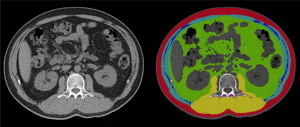

The AI software employed a U-net network (15) to segment fat and muscle regions in the CT images. The segmentation algorithm’s gold standard was established collaboratively by two radiologists: one served as the labeling radiologist and the other as the arbitration radiologist. The labeling radiologist independently reviewed and annotated the subcutaneous adipose tissue (SAT) area, visceral adipose tissue (VAT) area, PM area, and paravertebral intramuscular fat (PIMF) area, spanning from the first to the fourth lumbar vertebra. These annotations were then reviewed by the arbitration radiologist. Prior to arbitration, the arbitration radiologist conducted a spot check of the labeling radiologist’s annotations. Once the spot check was confirmed, the arbitration radiologist reviewed and resolved any ambiguities in the annotated data. The arbitration radiologist could edit the annotations if necessary, resulting in a final, consensus annotated dataset. For annotation, the Insight Toolkit-SNAP (ITK-SNAP) software (version 3.8.0, available at http://www.itksnap.org/pmwiki/pmwiki.php) was employed. A total of 402 high-quality annotated datasets were created, covering chest and abdominal CT scans. These annotated datasets were used to develop and train a segmentation model, which demonstrated high accuracy and reliability in biomedical image segmentation tasks (16). The segmentation results are shown in Figure 1.

In this study, we utilized the U-net segmentation model to achieve fully automated segmentation of SAT, VAT, PMs, and PIMF. In cases of segmentation errors, manual fine-tuning was performed by a radiologist. By integrating the segmentation results with image spacing information, we were able to calculate the area and mean CT values for each tissue component. The AI software computed the areas of SAT, VAT, PM, and PIMF based on the number of pixels labeled by distinct color masks, with all area measurements reported in square centimeters (mm2). The mean CT values of PM, in Hounsfield units (HU) (17), were obtained by averaging the pixel values within the designated PM region. To quantify the degree of PIMF, we developed a method based on area ratios. Specifically, we calculated the ratio of the PIMF area to the combined area of PM and PIMF. This ratio provides a direct measure of the distribution of adipose tissue within the PM.